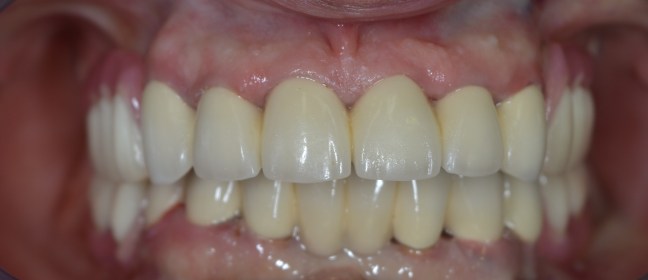

Funkcionális és esztétikai kezelés: harapás korrigálása a fogív kiegyenesítése, fogak közötti rések szűkítése, kereszt harapás megszüntetése az összes megmaradt fog koronázásával. A hiányzó hátsó fogak pótlása implantátumokon megtámasztott koronákkal.

Protetikai munka elkészülésének ideje: 10 munkanap

Koronák anyaga: fémkerámia

Fogszín: A1.